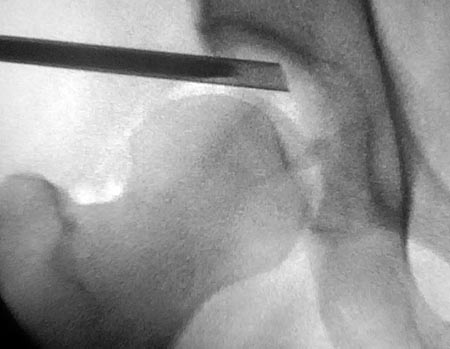

Para realizar las artroscopía de cadera utilizamos anestesia raquídea combinada con sedación profunda del paciente. El correcto posicionamiento en decúbito dorsal del paciente sobre mesa de tracción es el primer paso hacia un procedimiento exitoso (Fig. 7).4

Figura 7: Posición decúbito dorsal. Mesa de tracción.

Figura 8: Vista radioscópica, distracción.

La tracción aplicada al miembro afectado oscila entre 11 y 23 Kilogramos, obteniendo aproximadamente un centímetro de distracción femoroacetabular (Fig. 8).